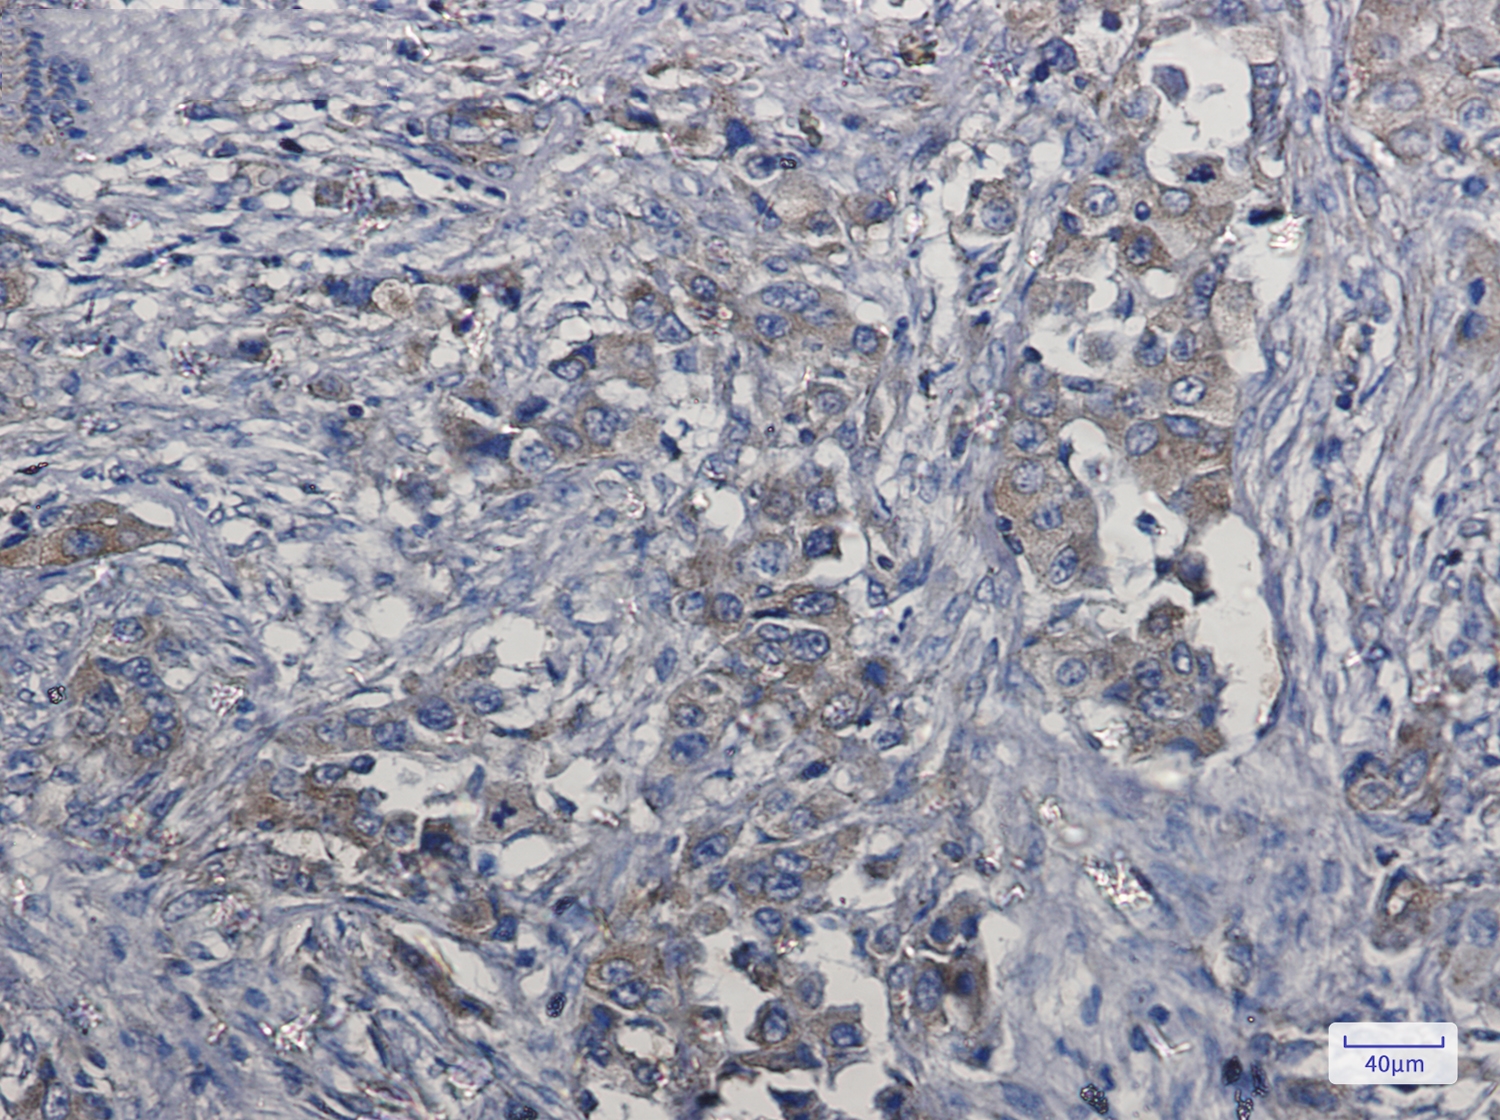

![c Met Rabbit mAb[52414]](https://img1.dxycdn.com/p/s14/2025/0922/957/4878302295998399691.jpg)

Immunohistochemistry of Met (c-Met) in paraffin-embedded Human lung cancer tissue using Met (c-Met) Rabbit mAb at dilution 1/5